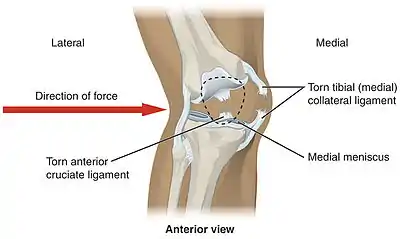

The medial collateral ligament (MCL a.k.a. "tibial") stretches from the medial epicondyle of the femur to the medial tibial condyle. It is composed of three groups of fibers, one stretching between the two bones, and two fused with the medial meniscus. The MCL is partly covered by the pes anserinus and the tendon of the semimembranosus passes under it.[10]: 206 It protects the medial side of the knee from being bent open by a stress applied to the lateral side of the knee (a valgus force).[10]: 206

The lateral collateral ligament (LCL a.k.a. "fibular") stretches from the lateral epicondyle of the femur to the head of fibula. It is separate from both the joint capsule and the lateral meniscus.[10]: 206 It protects the lateral side from an inside bending force (a varus force). The anterolateral ligament (ALL) is situated in front of the LCL.

In sports that place great pressure on the knees, especially with twisting forces, it is common to tear one or more ligaments or cartilages. Some of the most common knee injuries are those to the medial side: medial knee injuries.[29]

Anterior cruciate ligament injury

The anterior cruciate ligament is the most commonly injured ligament of the knee. The injury is common during sports. Twisting of the knee is a common cause of over-stretching or tearing the ACL. When the ACL is injured a popping sound may be heard, and the leg may suddenly give out. Besides swelling and pain, walking may be painful and the knee will feel unstable. Minor tears of the anterior cruciate ligament may heal over time, but a torn ACL requires surgery. After surgery, recovery is prolonged and low impact exercises are recommended to strengthen the joint.[30]